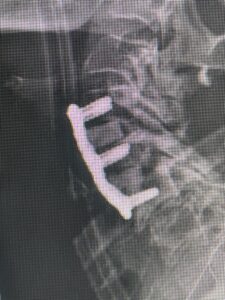

(Fig. 3) lateral intraoperative cervical x-ray demonstrating good alignment after C4-C6 anterior cervical discectomy and interbody fusion with plate. Note the interbody grafts help load-share the plate in this patient with severe osteoporosis

Because she had failed conservative management of her lumbar stenosis and spondylolisthesis it was decided to perform a lumbar laminectomy and fusion of the L5-S1 segment. Because of her history of severe osteoporosis and hardware cut-out from the bone, we decided to offer her hydroxyapatite-coated screws to provide fixation of her L5-S1 segment (Fig. 4a and b)